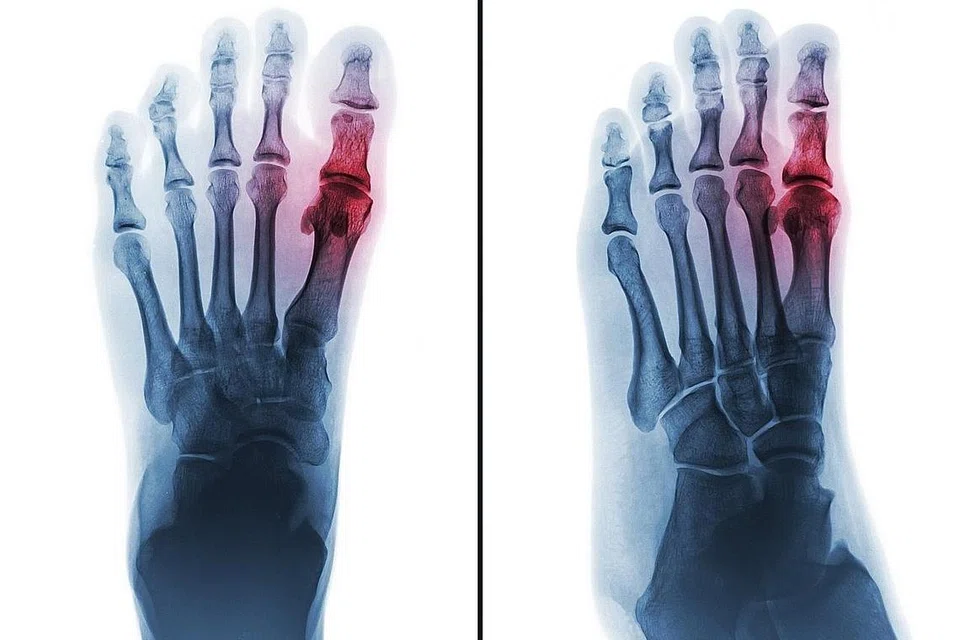

ANTARA PENYAKIT PALING LAMA: Gout adalah sejenis penyakit disebabkan berlebihan asid urik di dalam badan. Bagi penghidap gout, asid urik yang berlebihan tidak dibuang dan berkumpul di dalam sendi. - Foto ISTOCKPHOTO -